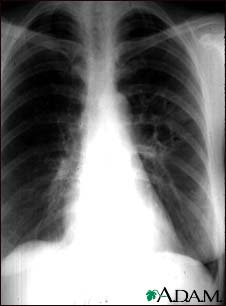

Coccidioidomycosis - chest X-ray

This chest x-ray shows the affects of a fungal infection, coccidioidomycosis. In the middle of the left lung (seen on the right side of the picture) there are multiple, thin-walled cavities (seen as light areas) with a diameter of 2 to 4 centimeters. To the side of these light areas are patchy light areas with irregular and poorly defined borders.

Other diseases that may explain these x-ray findings include lung abscesses, chronic pulmonary tuberculosis, chronic pulmonary histoplasmosis, and others.